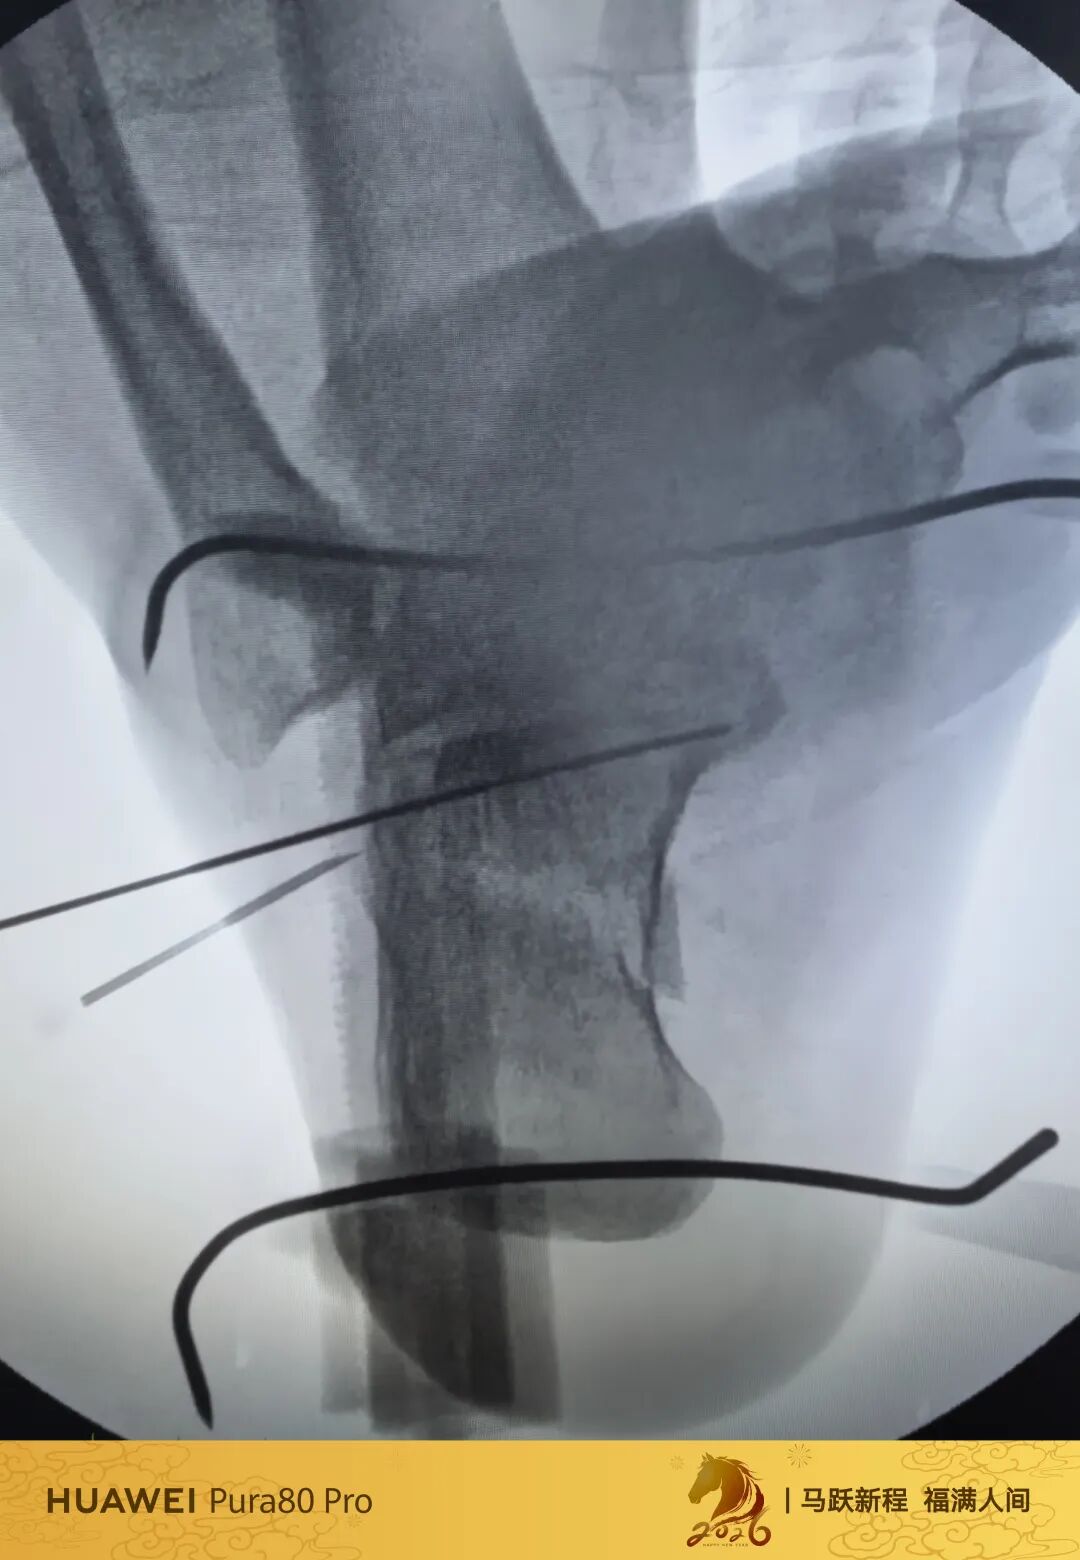

可透视撑开器

高温高压已经消毒10次

低温等离子已经消毒4次

目前来说依旧强硬

强度没问题

高分子材料

质量没得说